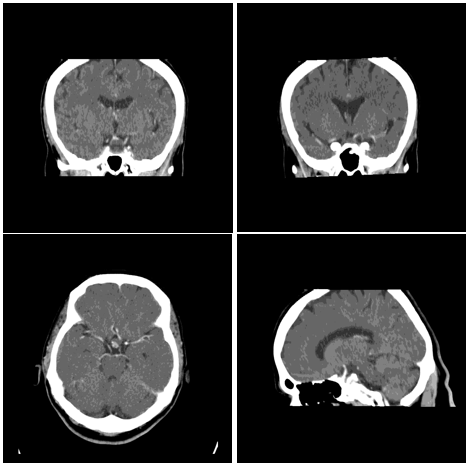

11. Urgent CT-Scan 30.01.08 (Figure 3).

12. Normal ventricular system, no shift of midline structures…

13. A ring of calcification is seen in the suprasellar region which looks like part of a hypodense lesion extending to Sella

14. ? Supra sellar aneurysm

15. ? Pituitary Tumor

16. CT with contrast is advised (Figure 3).

Figure 3